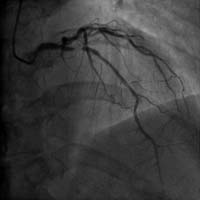

冠心病介入診療技術(shù):包括冠狀動脈造影術(shù)、經(jīng)皮冠狀動脈腔內(nèi)成形及支架術(shù)(PCI)、經(jīng)橈動脈冠狀動脈介入治療(TRI)、血流儲備分數(shù)(FFR)測定等。介入團隊24小時候命,能勝任急診PCI。對慢性閉塞性病變(CTO)的治療亦達到國內(nèi)先進水平。

右冠狀動脈閉塞 介入術(shù)后右冠開通

前降支近端嚴重狹窄 介入術(shù)后狹窄消失

介入手術(shù)治療嚴重冠心病